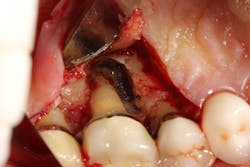

Figure 3: Tooth that would normally need to be extracted and replaced with an implant

The advent of laser technology, either as an adjunct to surgical therapy or as a monotherapy, has been met with mixed results in the literature.13 Recently, a new 9.3-micron CO2 laser (Solea from Convergent Dental) with the ability to cut both hard and soft tissue with efficiency was introduced to the dental market. This laser can penetrate deep defects with enough power to both thoroughly detoxify root surfaces and remove fibrous tissue, enhancing tissue repair (figure 2).14 The spot size of the focal laser beam can also be controlled to a range of .25 mm to 1.25 mm so that the beam can be directed into furcation entrances. This allows previously difficult furcal defects to be detoxified prior to regenerative therapy. Because of this enhanced ability to detoxify, this laser has been able to change the prognosis of once-hopeless teeth (figure 3) and allow for tissue regeneration (figure 4) instead of extraction.

Figure 4: Same tooth one year later after laser detoxification and periodontal regeneration with growth-stimulating factors